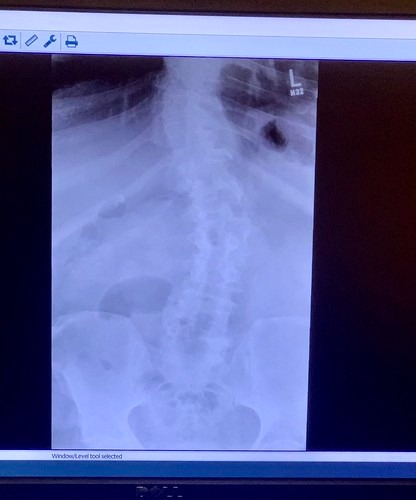

ケース③骨の変化を原因とする腰椎捻挫

曲がった背骨が写るレントゲン写真

Tobyotter

重量物を取り扱う時間が、労働時間の一定割合以上を占める業務に就いていた場合も、労災の対象となりえます。対象となる業務は、30kg以上の物品では労働時間の3分の1以上、20kg以上の物品では労働時間の2分の1以上を占めるものです。

こうした職種に約10年以上従事し、骨が変化したことによって、腰椎捻挫を発症した場合、労災の対象となります。また、仕事を休む場合は休業損害の対象です。